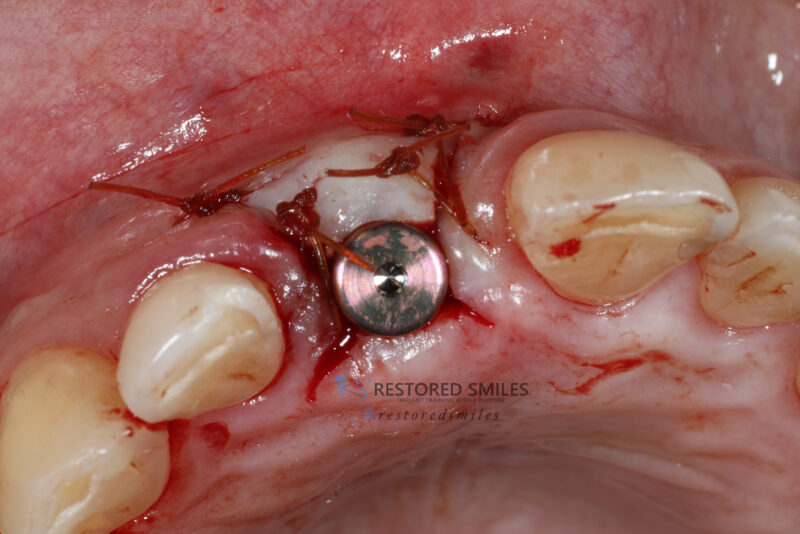

• This was a tough case with a large through-and-through defect on an upper central incisor. After the area was throughly cleansed I grafted using mineralized cortical particulate with CGF/PRF protocols. A thick collegen resorbable membrane was secured with membrane stabilizing sutures and primary closure achieved with a nonresorbable PTFE…

Read more